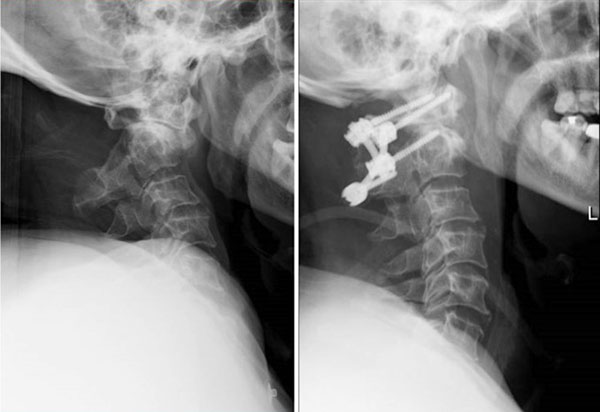

术前术后X对比